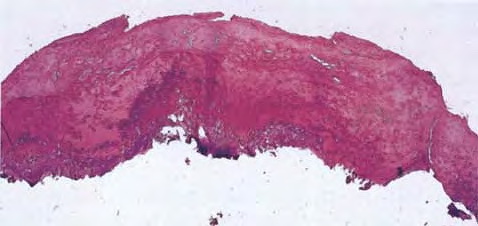

Orf = الاورف